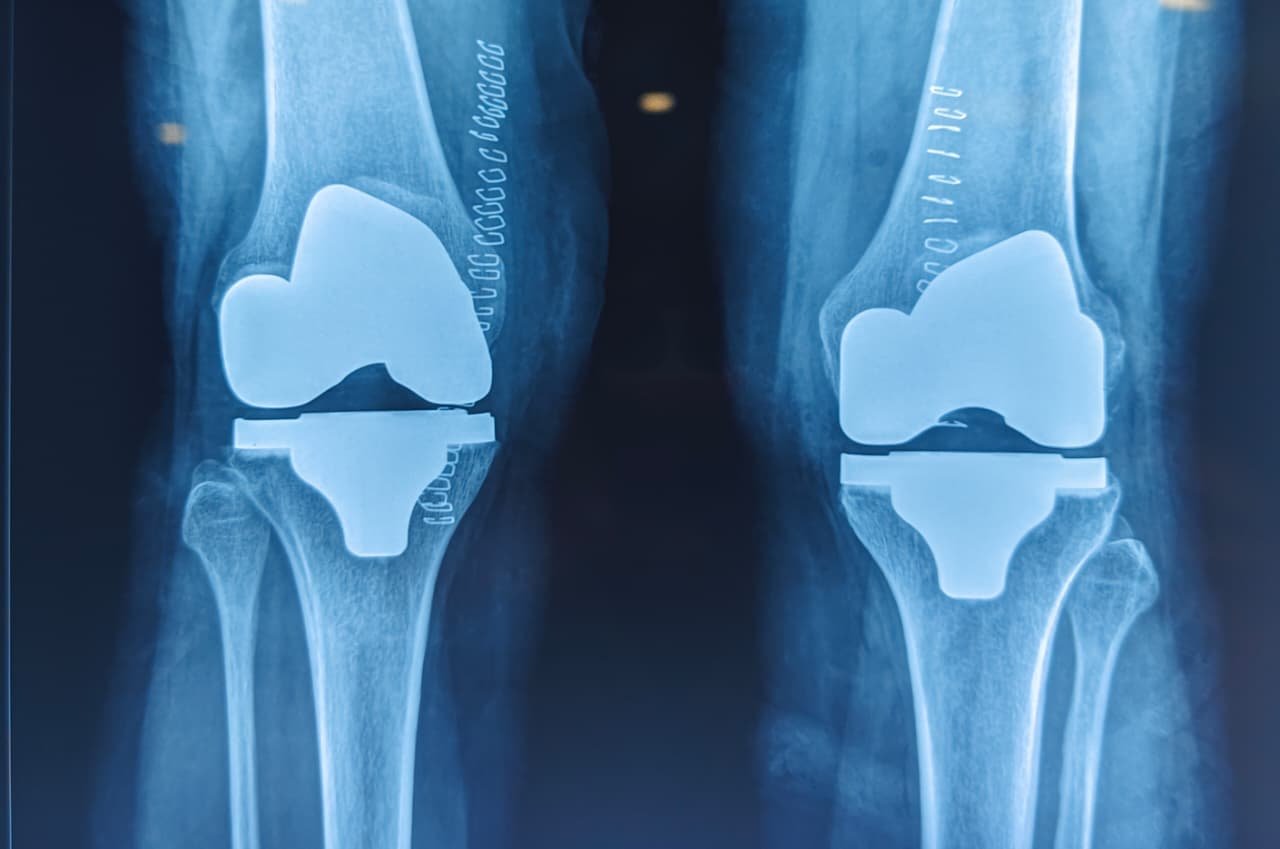

Joint Replacement (Robotic & Conventional):

◆ Total knee replacement

◆ Total hip replacement for AVN,arthritis etc

◆ Hemiarthroplasty

◆ Total shoulder arthroplasty

◆ Reverse shoulder arthroplasty